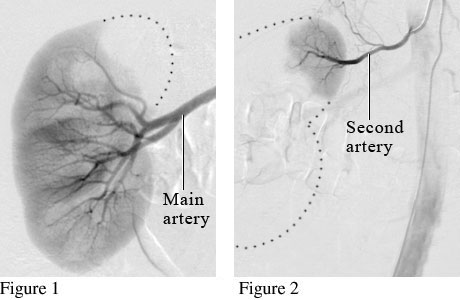

Angiogram of a Normal KidneyCourtesy of Intermountain Medical Imaging, Boise,

Idaho. Many people have more than one artery for blood flow to the

kidneys. Figure 1 is an angiogram showing the main artery supplying blood flow to the kidney. Figure 2 is an angiogram showing a second artery helping to supply blood to the kidney. ByHealthwise Staff Primary Medical ReviewerRakesh K. Pai, MD, FACC - Cardiology, Electrophysiology Specialist Medical ReviewerHoward Schaff, MD - Diagnostic Radiology Current as ofOctober 14, 2016 Current as of: